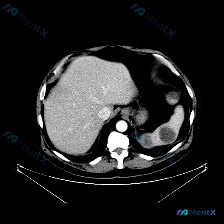

今天整理了一个很有警示意义的影像病例,核心是单张平扫CT下的脾脏病变,想和大家一起梳理下完整的分析思路。 先看影像核心发现 - 定位:上腹部CT软组织窗,左侧脾脏层面 - 关键异常: 1. 脾脏肿大; 2. 脾实质内见大范围、边界尚清晰但密度不均匀的低密度影,形态呈相对弥漫或片状,主要占据后部及部分...

最近看到一份腹部平扫CT的影像资料,主要异常集中在脾脏,整理了一下读片和分析思路,和大家分享。 先整理一下核心影像事实 这是一张腹部CT软组织窗横断面图像,主要发现如下: 1. 肝脏:实质密度尚均匀,未见明确局灶性占位,肝叶比例、血管走行基本正常 2. 脾脏:形态正常,但脾实质内可见一个圆形、边界相...

今天整理了一份上腹部增强CT的影像资料,结合临床分析思路,觉得挺有讨论价值的,分享给大家。 影像核心发现 上腹部增强扫描(软组织窗): - 肝脏:轮廓光滑,密度均匀,未见明确局灶性病变; - 脾脏:体积增大,实质内见多发圆形/类圆形低密度灶,边界相对清晰,增强后无强化或强化程度远低于正常脾实质; -...

今天整理了一张很有启发的上腹部CT平扫影像,核心发现是脾脏内的多发类圆形低密度灶,想和大家一起梳理一下鉴别诊断的思路。 --- 先看影像的客观表现 这是一张上腹部横断面CT平扫(软组织窗): - 肝脏:形态大小、实质密度都还好,没看到明确占位,肝门血管也清晰; - 脾脏:是最显眼的地方——多个类圆形...